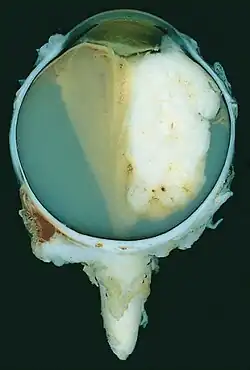

A pathology specimen of a retinoblastoma tumor from an enucleated eye of a 3-year-old female

Morphology

Gross and microscopic appearances of retinoblastoma are identical in both hereditary and sporadic types. Macroscopically, viable tumor cells are found near blood vessels, while zones of necrosis are found in relatively avascular areas. Microscopically, both undifferentiated and differentiated elements may be present. Undifferentiated elements appear as collections of small, round cells with hyperchromatic nuclei; differentiated elements include Flexner-Wintersteiner rosettes, Homer Wright rosettes,[31] and fleurettes from photoreceptor differentiation.[32]